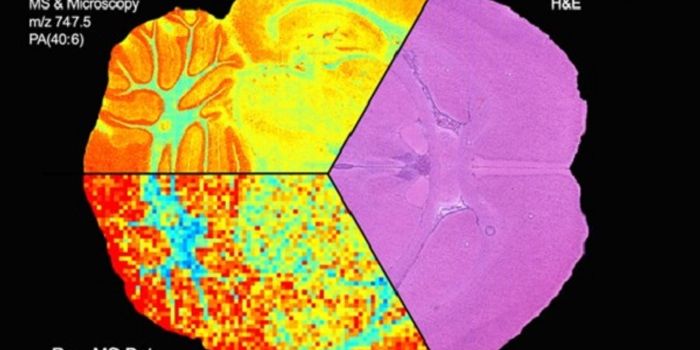

MAR 17, 2015CancerVanderbilt University researchers have achieved the first "image fusion" of mass spectrometry and microscopy - a technic ...